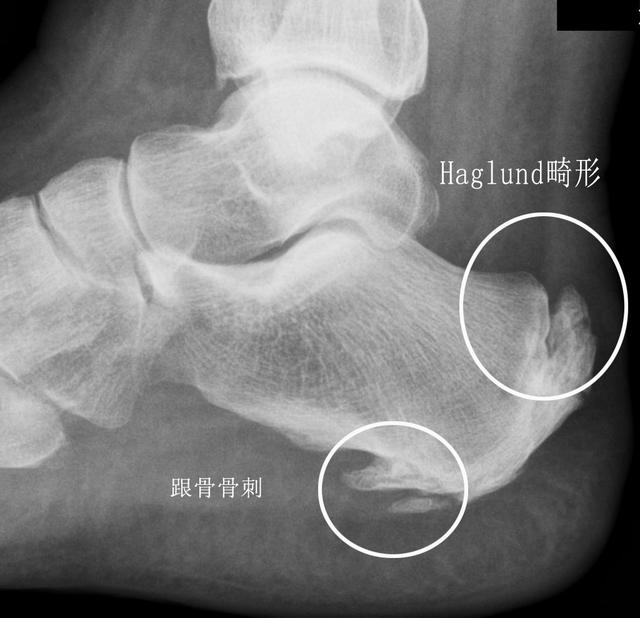

Haglund综合征诱发的跟骨痛

这种疾病其实并不少见,只是很多时候并没有被诊断出来,只是当做了普通的跟腱炎去治疗了。下面这个患者就是谢医生在门诊发现的一例这种疾病的患者照片,看过之后大家就会对这种疾病有一个比较深的认识。

这个疾病有三个特点,就是跟腱止点处的无菌性炎症、骨性增生肥大以及皮下或跟腱下滑囊炎,这其中以骨性的增生肥大最为显著。在这个疾病的早期,骨质增生并不影响生活的时候,我们采取保守治疗的办法。当发展到晚期需要的治疗和其他的跟痛疾病不同,我们建议手术治疗,切除增生的骨赘,重建跟腱。